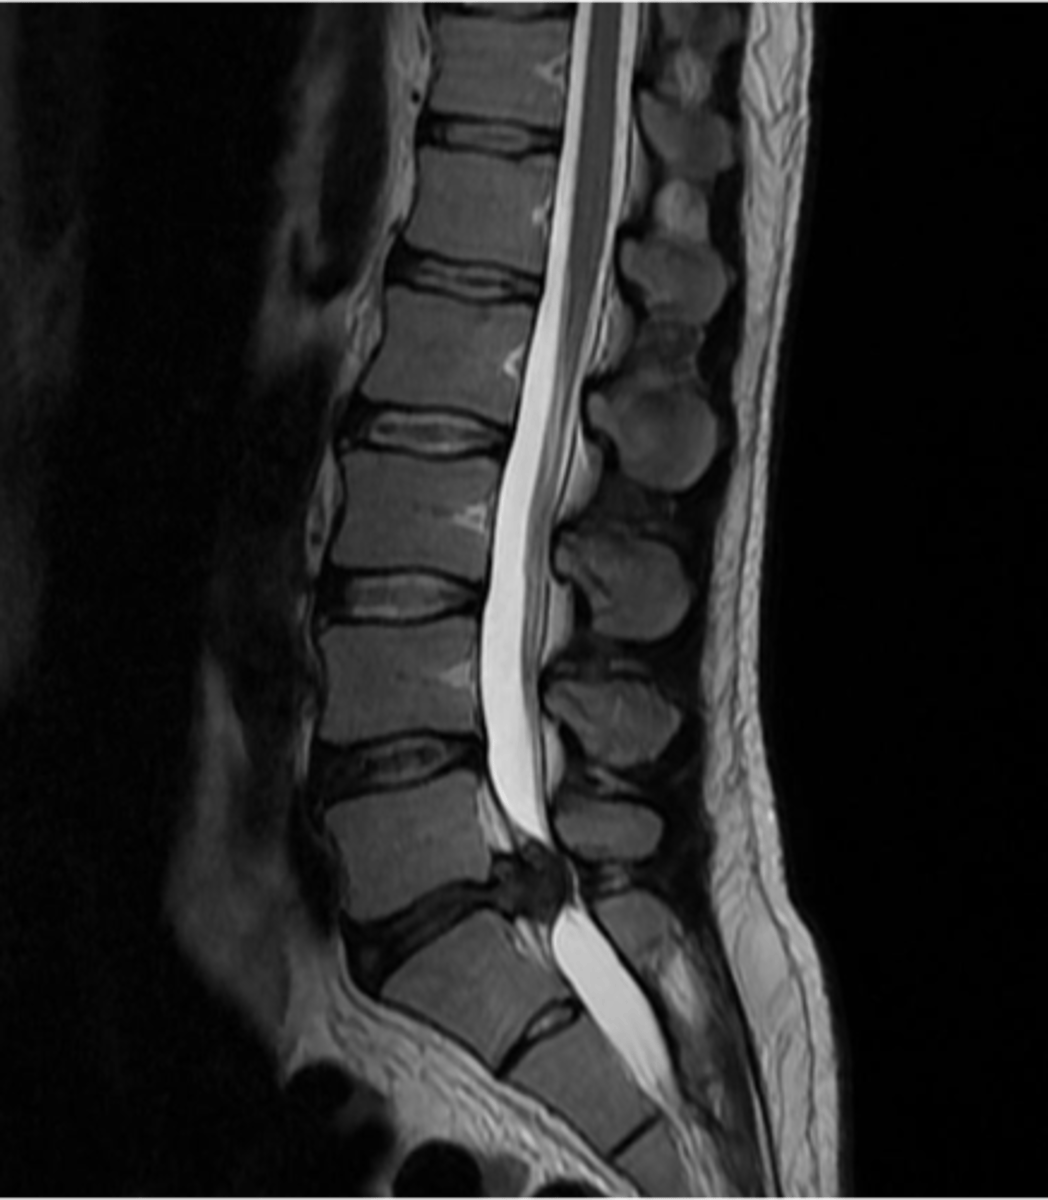

spondylosis

arthritic degeneration of the spine

spondylosis is generally accompanied by ____ formation and disc ______

osteophyte formation and disc thinning/collapse

_____ is a common cause of low back pain but can occur anywhere